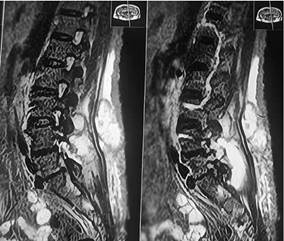

Al cuadro se suma alzas térmicas hasta 38,5 ° que ceden con paracetamol de forma parcial, taquicardia persistente y clínicamente presencia de fluctuación del nódulo proveniente de la línea media de la espalda por lo que se desde realizar una resonancia magnética de columna lumbosacra en la cual se observa colección en planos superficiales posteriores (paraespinosos), y otras colección que se dirige hacia canal medular a nivel de L4-L5, además de protrusión discal L4-L5 subarticular derecha sin compromiso radicular y protrusión discal subarticular derecha de L5-S1 con compromiso radicular ipsilateral, hiperdensidad de apofisis espinosas de L3-L4.

En resonancia magnética, los cambios son visibles de forma precoz a 3 o 5 días desde el inicio de la infección, con una sensibilidad del 96% y especificidad del 93%. Por esto mismo, las guías IDSA 2015 recomiendan el estudio con resonancia magnética en todos los pacientes con sospecha de infección espinal. Los cambios característicos en resonancia magnética dependen de la secuencia que se esté analizando. En secuencia T1, se encontrará hipo intensidad de señal del cuerpo y plataforma vertebral, así como del disco intervertebral comprometido y borramiento del límite cuerpo-disco. En secuencia T2, veremos hiperintensidad de señal del cuerpo y plataforma vertebral, así como del disco intervertebral comprometido y pérdida de la hendidura intranuclear característica. Finalmente, en la secuencia con gadolinio, destacará el refuerzo periférico en anillo de las lesiones del cuerpo, plataforma y disco.8

El diagnóstico de una colección vertebral generalmente se realiza mediante estudios de imagen (como resonancia magnética, que es la prueba más sensible para identificar abscesos epidurales o espondilodiscitis) y análisis de sangre (para detectar signos de infección, como leucocitosis o elevación de la proteína C reactiva). El tratamiento depende de la causa subyacente y puede incluir antibióticos, drenaje quirúrgico.